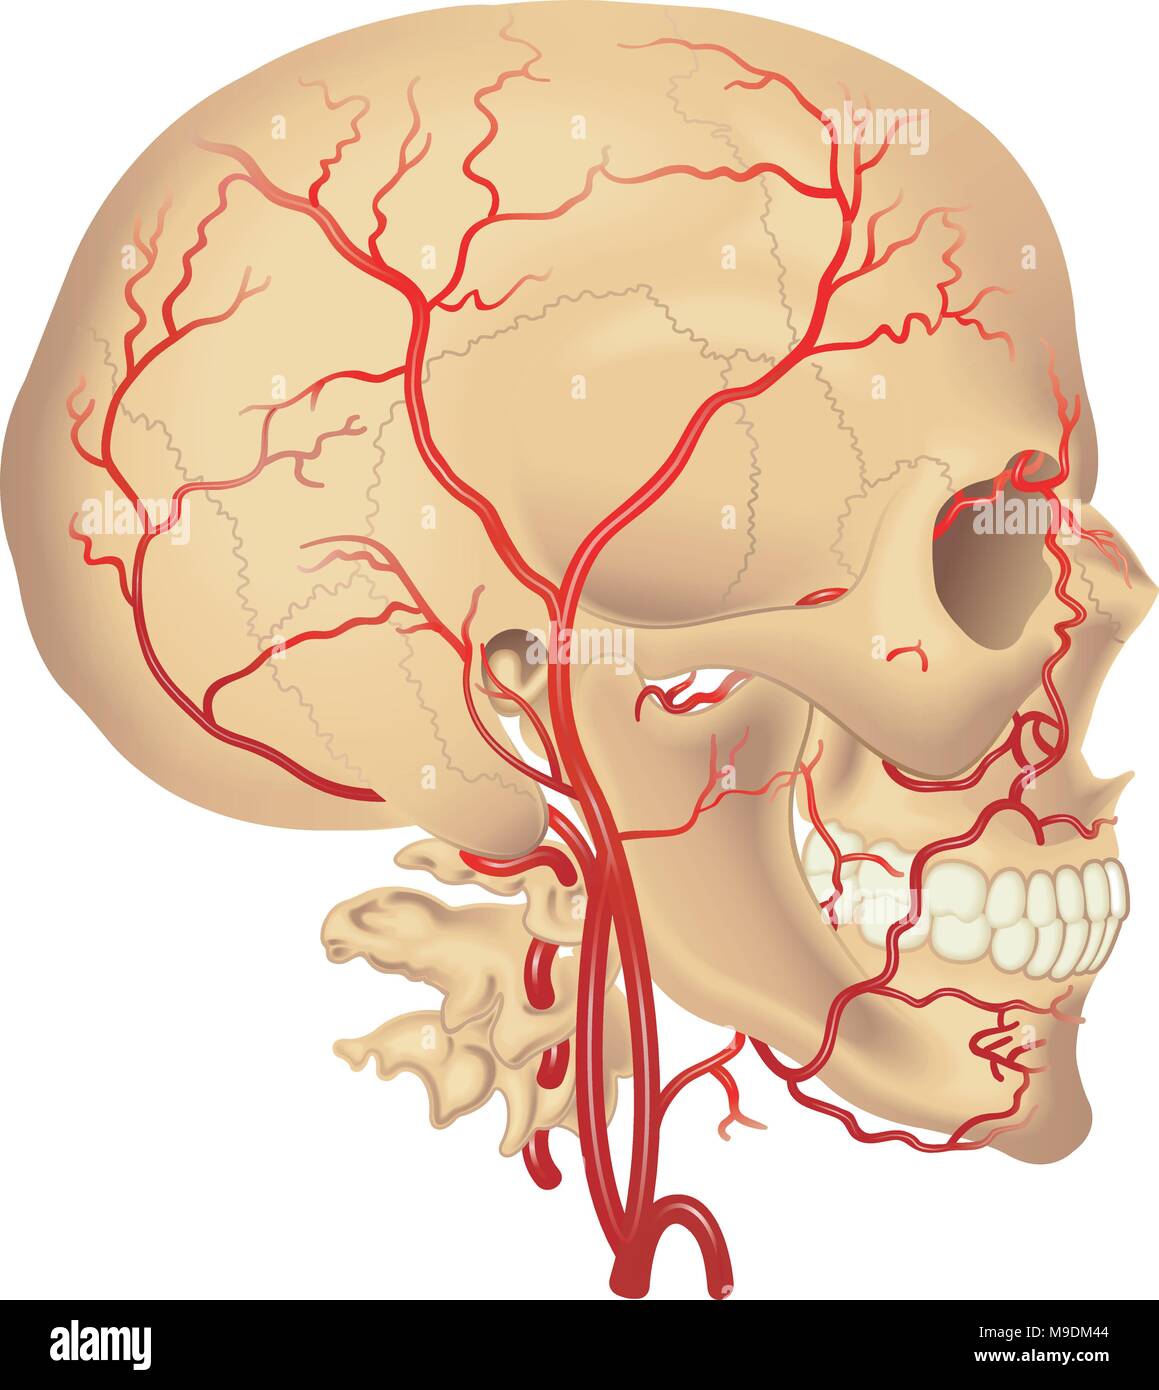

RMJE9NWM–Dieses anatomische Bild zeigt die Arterien unter dem Gehirn, einem wichtigen Teil des menschlichen Kreislaufsystems. Die Arterien sind dafür verantwortlich, das Gehirn mit Blut zu versorgen und seine Funktion zu gewährleisten. Die Nahansicht hilft beim Verständnis ihrer Struktur und Rolle für die Gesundheit und Funktion des Gehirns.

RF3C7H8AB–Darstellung der arteriellen Blutversorgung des Gehirns mit hervorgehobener Arteria cerebri Media (gelb), die Blut zu den frontalen, temporalen und parietalen Lappen liefert, entscheidend für die Gehirnfunktion.

RF3C7H897–Darstellung der arteriellen Blutversorgung des Gehirns mit hervorgehobener Arteria cerebri Media (gelb), die Blut zu den frontalen, temporalen und parietalen Lappen liefert, entscheidend für die Gehirnfunktion.

RF3C7H892–Darstellung der arteriellen Blutversorgung des Gehirns mit hervorgehobener Arteria cerebri Media (gelb), die Blut zu den frontalen, temporalen und parietalen Lappen liefert, entscheidend für die Gehirnfunktion.

RF3C7H890–Darstellung der arteriellen Blutversorgung des Gehirns mit hervorgehobener Arteria cerebri Media (gelb), die Blut zu den frontalen, temporalen und parietalen Lappen liefert, entscheidend für die Gehirnfunktion.

RM2JYR3FK–Thomas Willis war ein berühmter englischer Arzt und Anatom aus dem 17. Jahrhundert, der vor allem für seine Arbeit über das Gehirn und das Nervensystem bekannt war. Er trug maßgeblich zum Verständnis des Kreislaufsystems bei, einschließlich der Beschreibung des Kreises von Willis, einem kritischen Bereich der Blutversorgung des Gehirns. Willis’ Arbeit legte Grundprinzipien in der Neuroanatomie und Physiologie.